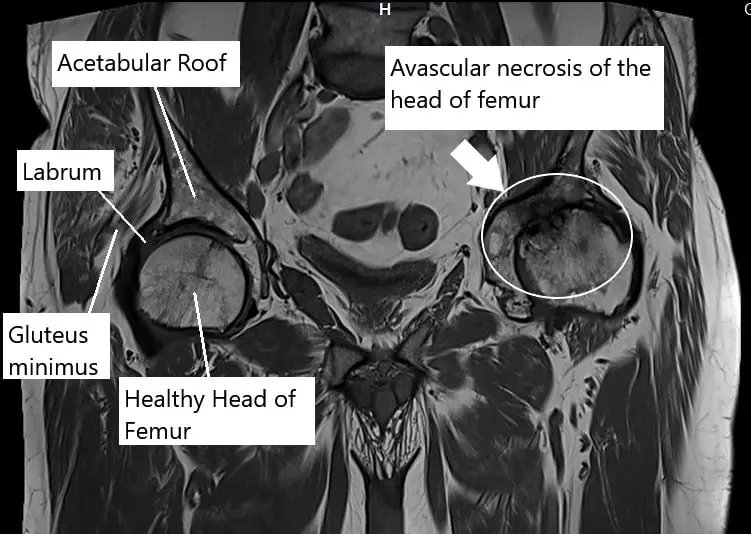

- MRI : It offers early detection even before the symptoms appear. Entailing the details of the tissues forming and surrounding the joint. Cartilage destruction, bone marrow and segments involved are easily detected.

MRI showing AVN hip

Any infections or edema(swelling) in the joint is also visualized. Any changes in the other hip which might get involved in the future can be detected.